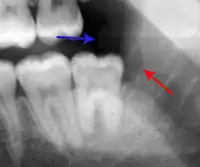

- The radiographic appearance of the local bone can become more radiopaque in chronic pericoronitis.[8]

The presence of dental plaque or infection beneath an inflamed operculum without other obvious causes of pain will often lead to a pericoronitis diagnosis; therefore, elimination of other pain and inflammation causes is essential. For pericoronal infection to occur, the affected tooth must be exposed to the oral cavity, which can be difficult to detect if the exposure is hidden beneath thick tissue or behind an adjacent tooth. Severe swelling and restricted mouth opening may limit examination of the area.[11] Radiographs can be used to rule out other causes of pain and to properly assess the prognosis for further eruption of the affected tooth.[12]

- Dental caries (tooth decay) of the wisdom tooth and of the distal surface of the second molar is common. Tooth decay may cause pulpitis (toothache) to occur in the same region, and this may cause pulp necrosis and the formation of a periapical abscess associated with either tooth.

- Food can also become stuck between the wisdom tooth and the tooth in front, termed food packing, and cause acute inflammation in a periodontal pocket when the bacteria become trapped. A periodontal abscess may even form by this mechanism.